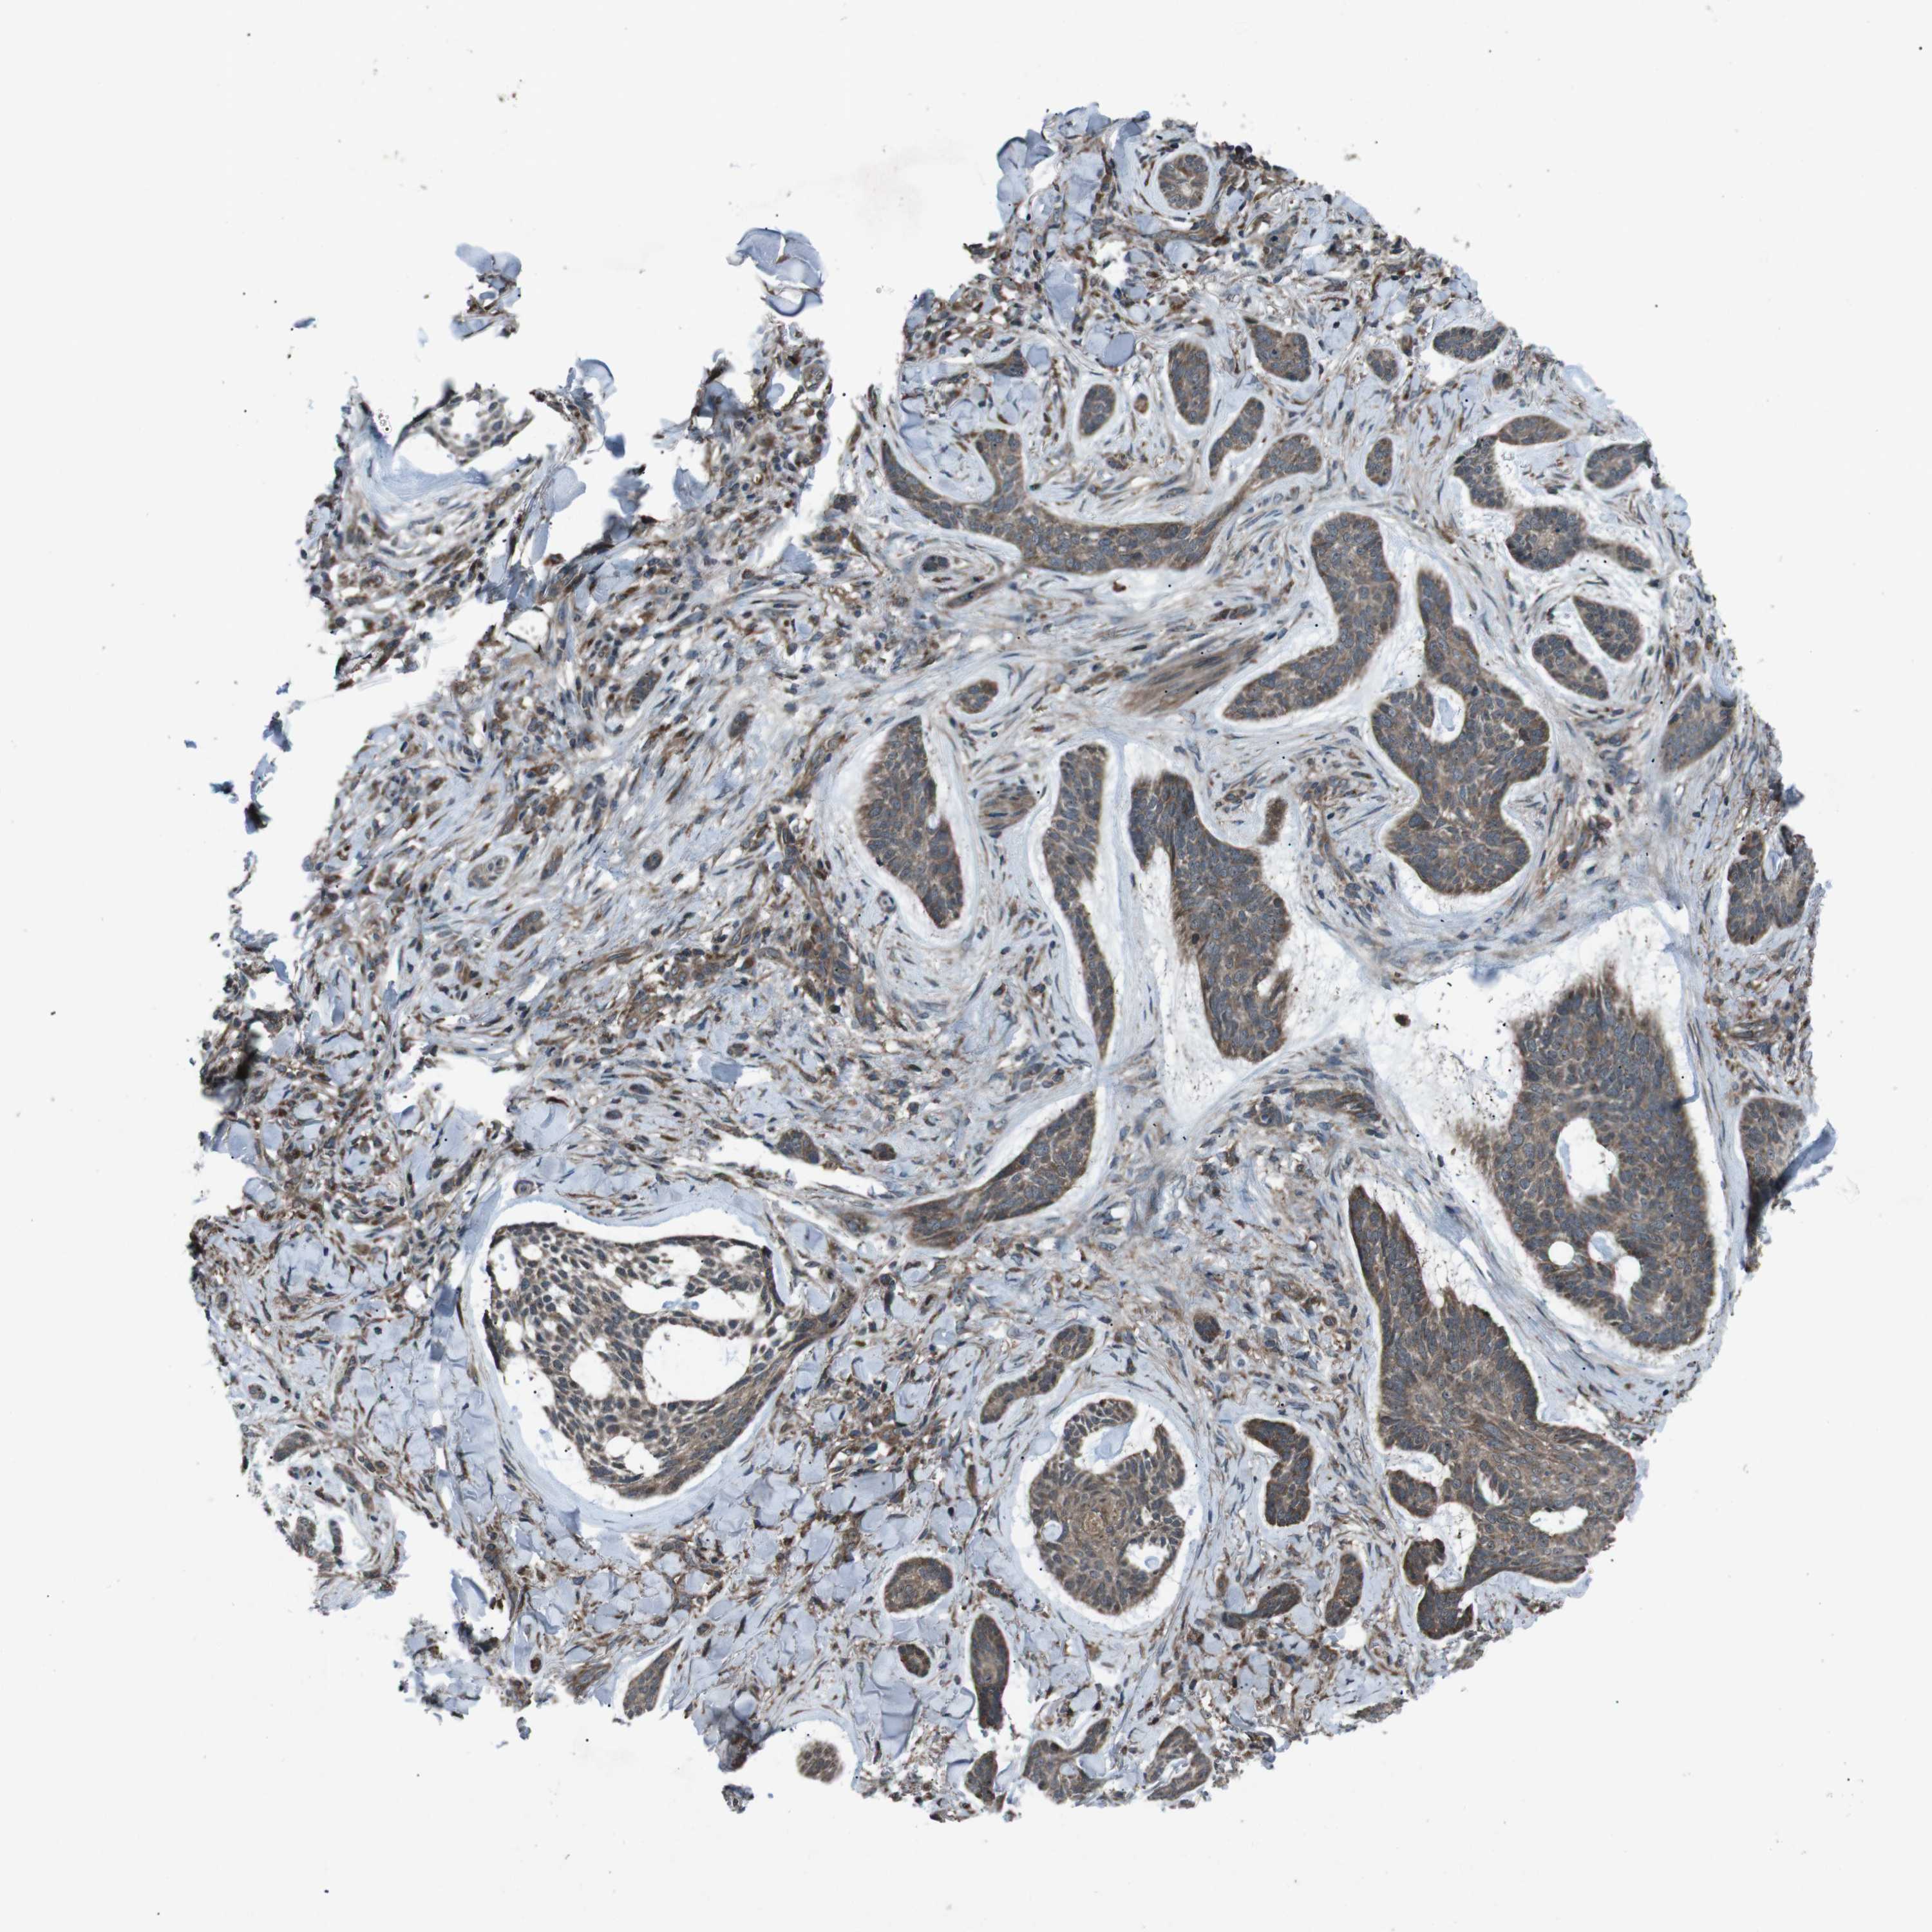

CANCER SKIN CANCER Show tissue menu

Basal cell and squamous cell cancer

SKIN CANCER - Protein expressioni

A mouse-over function shows sample information and annotation data. Click on an image to view it in a full screen mode. Samples can be filtered based on level of antibody staining by selecting one or several of the following categories: high, medium, low and not detected. The assay and annotation is described here.

Each image is clickable and will lead to virtual microscopy that enables deeper exploration of all samples and also displays staining intensity scores, fraction scores and subcellular localization as well as patient and tissue information for each sample.

Antibody HPA007293

Squamous cell carcinoma, NOS

Squamous cell carcinoma, metastatic, NOS

Basal cell carcinoma

Papilloma, NOS

Squamous cell carcinoma in situ, NOS

Adnexal tumor, benign